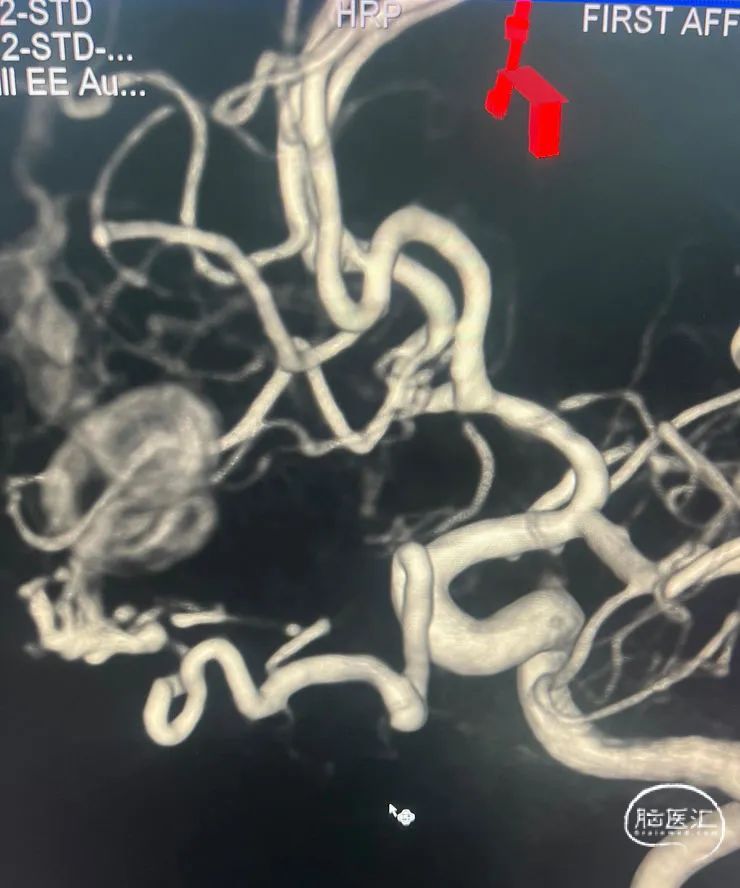

术前影像资料

术前3d

左侧比较粗,先解决主要矛盾,或许可以通过一根血管搞定。

看来动脉路有戏,但保证胶一定不要返流到视网膜中央动脉。比较了一下,左侧眼动脉比较粗,从左侧眼动脉走,动脉高压锅努力搞起💪。一方面,可以让胶勇往直前,另一方面,可以防止胶逆流。

两侧的眼动脉用不同的方法进入。左边直接用Echelon超选,用另外一根微导管做塞子,塞子做在视网膜中央动脉开口的远端。